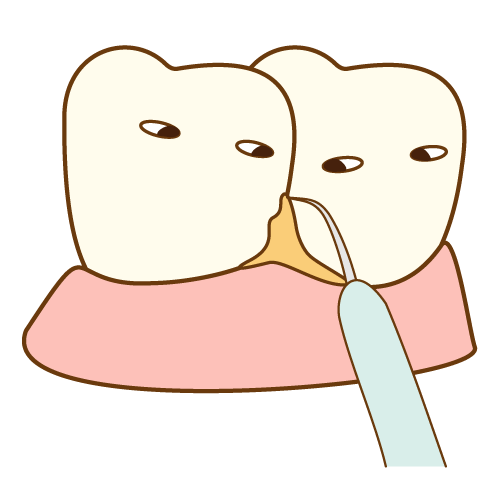

⑥ 前回詰めた綿花の状態を確認して、良い状態なら、「根管充填剤」(マスターポイント・アクセサリーポイント)というお薬を、余分な空間がないように根っこに詰めます。

⑥ 前回詰めた綿花の状態を確認して、良い状態なら、「根管充填剤」(マスターポイント・アクセサリーポイント)というお薬を、余分な空間がないように根っこに詰めます。 Q1.痛みはありますか?

Q1.痛みはありますか? ② 次に、「根管長測定器」という機械を使い、根っこの長さを正確に測ります。

② 次に、「根管長測定器」という機械を使い、根っこの長さを正確に測ります。

⑤ 次に、仮詰めをします。

⑤ 次に、仮詰めをします。 虫歯が神経まで達して炎症を起こしているので、人によってはズキズキとした痛みを感じる方もいます(>_<)

虫歯が神経まで達して炎症を起こしているので、人によってはズキズキとした痛みを感じる方もいます(>_<)